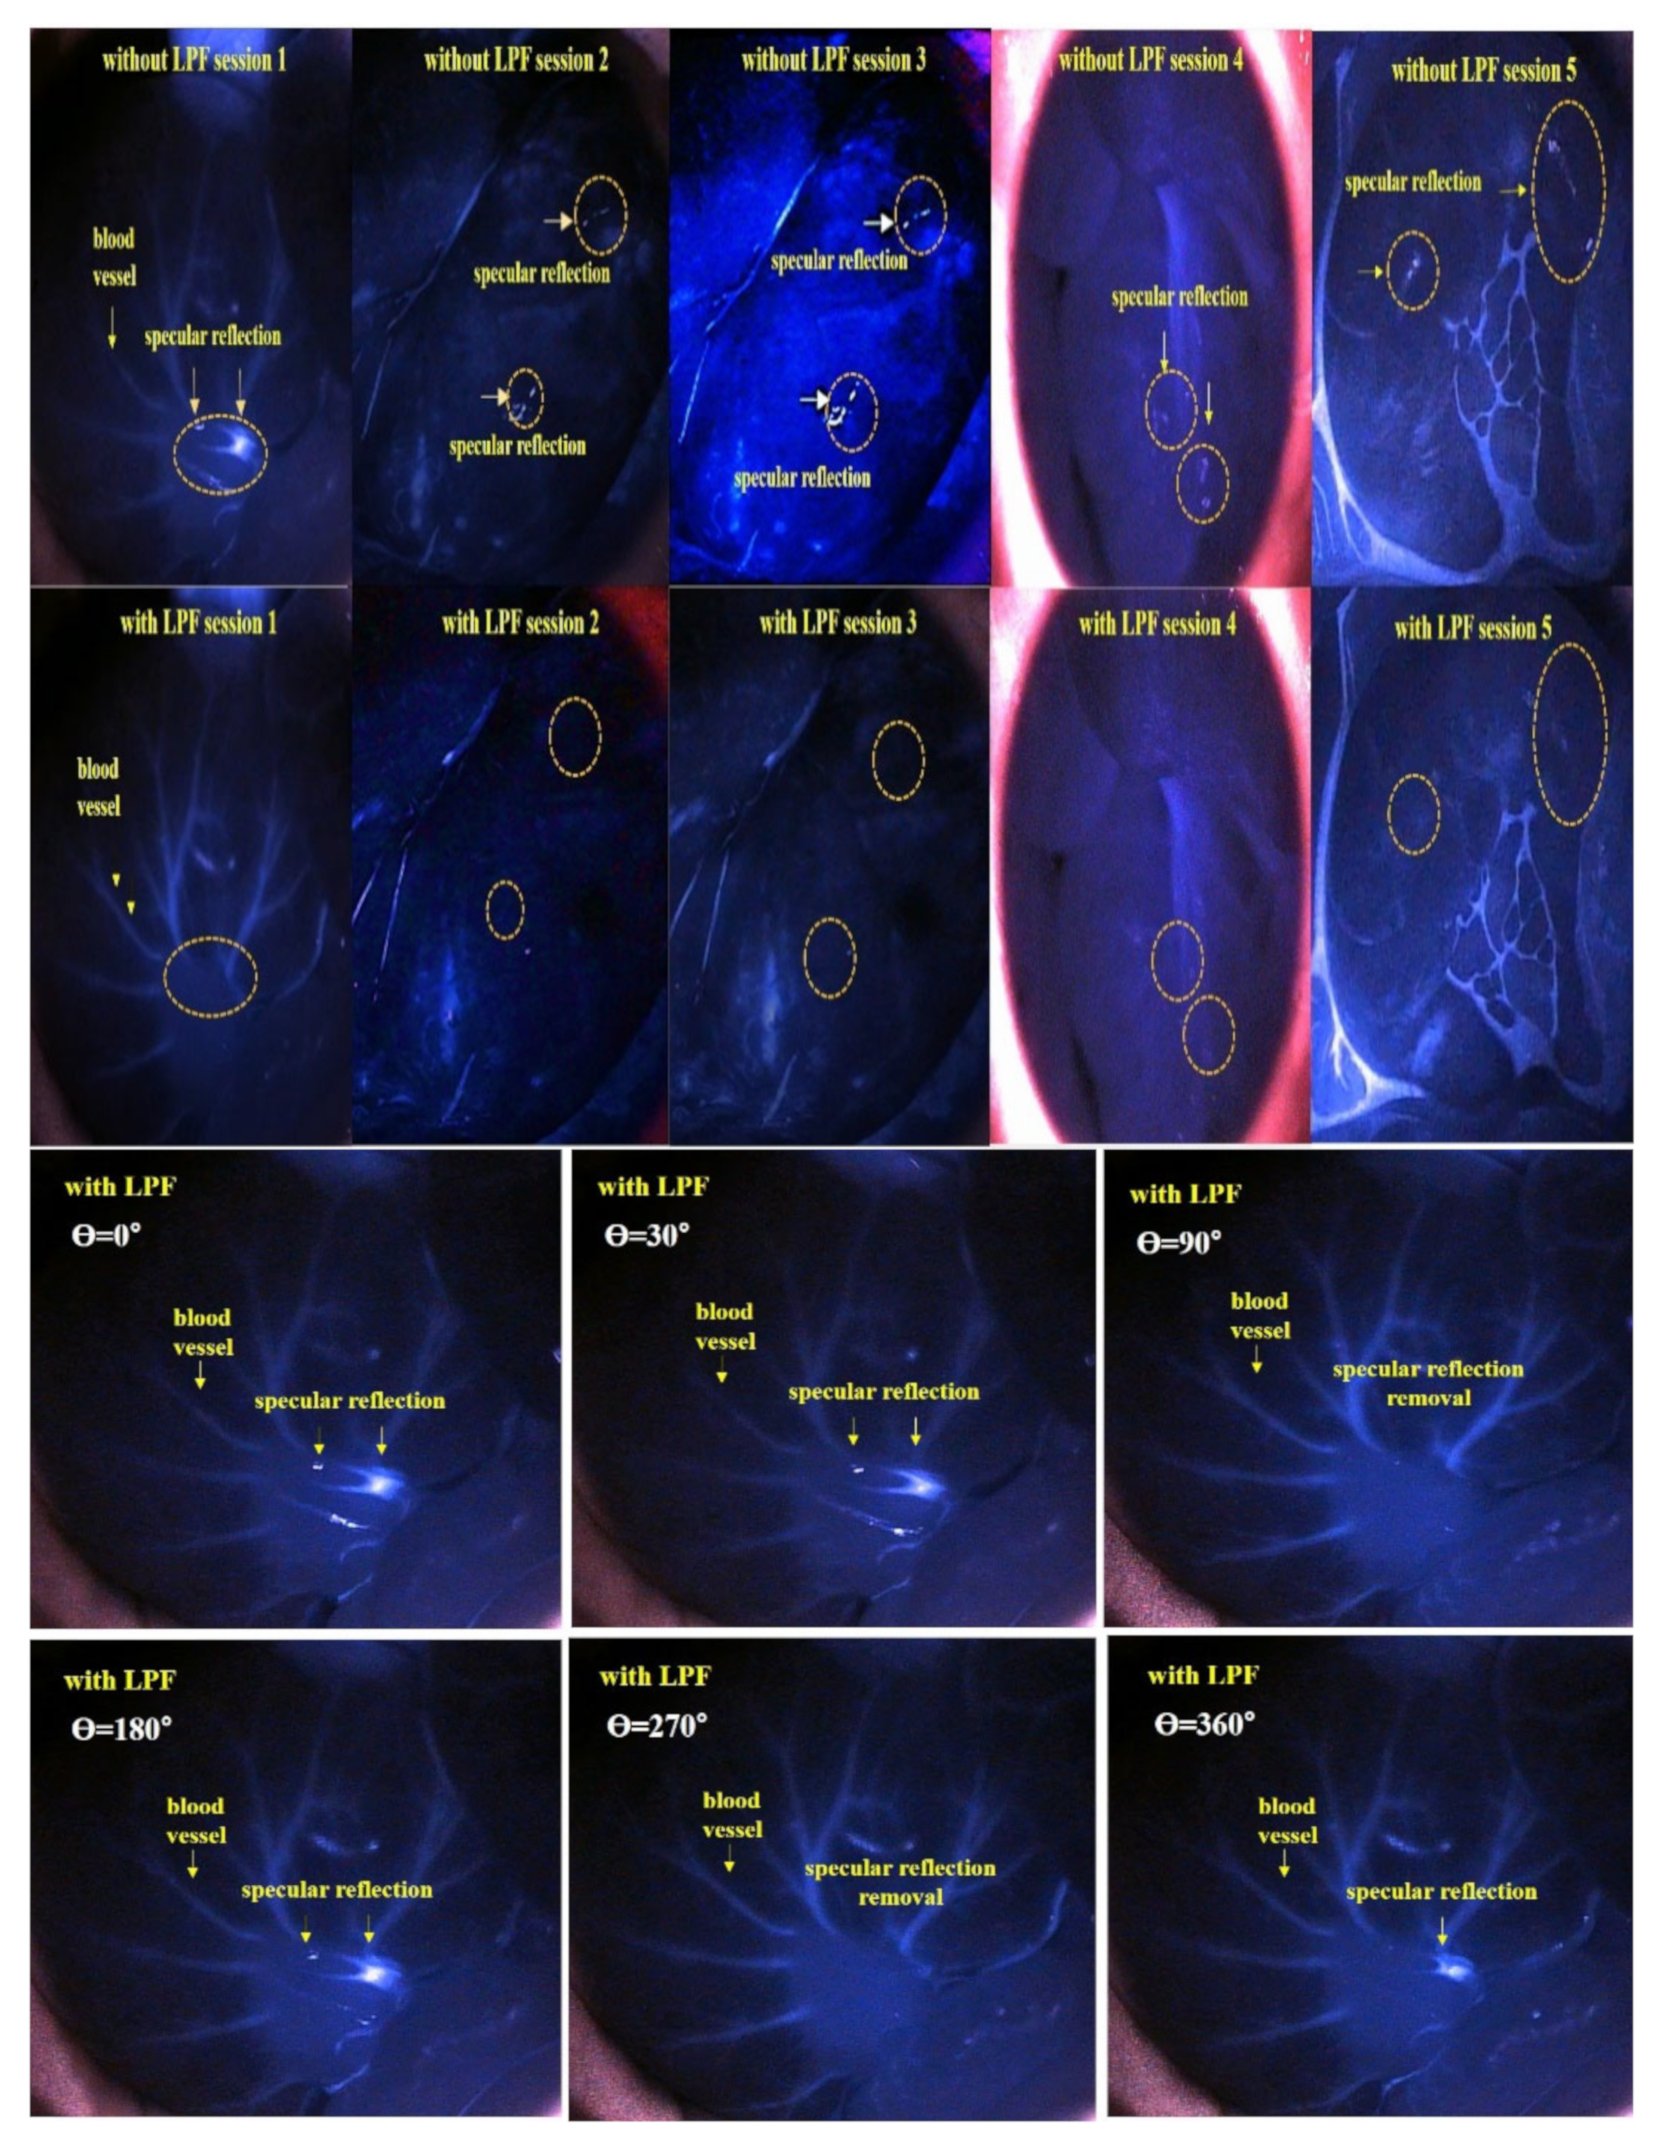

| Rotation Angle of the Filter F2 (θ) | Specular Reflection Intensity [mW/cm2] | Rotation Angle of Filter F2 (θ) | Specular Reflection Intensity [mW/cm2] |

|---|---|---|---|

| 0° | 50.0 | 210° | 37.5 |

| 30° | 37.5 | 240° | 12.5 |

| 60° | 50.0 | 270° | 0.00 |

| 90° | 0.00 | 300° | 12.5 |

| 120° | 12.5 | 330° | 37.5 |

| 150° | 37.5 | 360° | 50.0 |

| 180° | 50.0 |